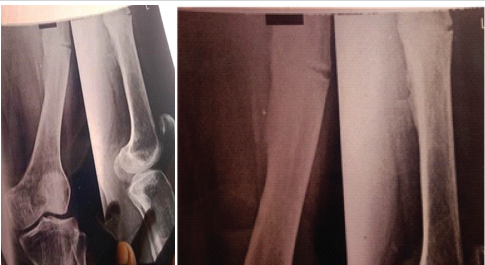

A 34-year-old female with known type ⅠA OI was admitted to our emergency department for a spontaneous left midshaft femur fracture on weight-bearing. She had a history of an atypical left femur fracture 1 month back, for which she was managed conservatively on oral medications. She also reported that she had a right femur fracture at 18 months of age while massaging, then had B/L upper limb forearm fractures while playing at around 8–10 years, all managed conservatively. The patient is of short stature with 1.30 m (Figs. 1 and 2).

Figure 1: X-rays of right atypical right femur fracture, which was managed conservatively.